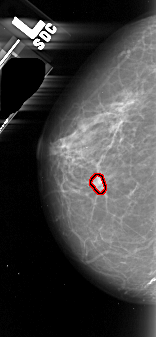

A_1102_1.LEFT_CC

LEFT_CC LINES 4381 PIXELS_PER_LINE 2026 BITS_PER_PIXEL 16 RESOLUTION 42 OVERLAY

FILE: A_1102_1.LEFT_MLO.OVERLAY

TOTAL_ABNORMALITIES 1

ABNORMALITY 1

LESION_TYPE MASS SHAPE IRREGULAR MARGINS ILL_DEFINED

ASSESSMENT 4

SUBTLETY 3

PATHOLOGY MALIGNANT

TOTAL_OUTLINES 1

BOUNDARY